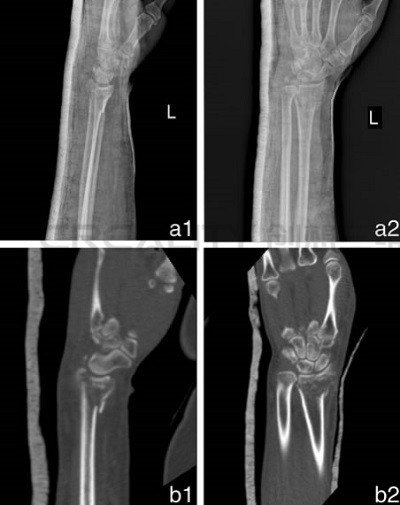

3D打印機(jī)制造模型如何改善骨折治療

中國(guó)研究人員正在研究使用3D打印機(jī)制造模型來(lái)改善骨折治療。第二附屬醫(yī)院骨科和浙江溫州醫(yī)科大學(xué)育英兒童醫(yī)院的華晨在“使用3D打印機(jī)制造的模型來(lái)改善骨折治療功效&rd...